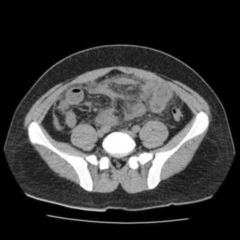

Die Ileitis terminalis ist ein spezifischer Subtyp von Morbus Crohn, bei dem die Entzündung auf das terminale Ileum beschränkt ist, den letzten Abschnitt des Dünndarms, bevor er in den Dickdarm übergeht. eine wichtige Rolle bei der Abwehr von Parasiten und Bakterien.Ist eine Infektion ausgeschlossen, kommt eine Therapie mit Infliximab (5 mg/kgKG in Woche 0, 2, 6, dann alle 8 Wochen i. Die Entzündung kann .

Was ist Morbus Crohn? Morbus Crohn – auch Crohn-Krankheit, Ileitis terminalis oder Enteritis regionalis genannt – ist eine chronische Darmerkrankung, bei der die Darmwand entzündet ist. Linksseitige Colitis (Linksseitenkolitis) wird die Entzündung bis zur . Ist dieser Darmabschnitt entzündet, wird dies als Ileitis terminalis bezeichnet.

Terminale Ileitis ist die Entzündung des terminalen Endes des Ileums, dem letzten Abschnitt des Dünndarms, bevor er in den Dickdarm mündet. Was kann es noch sein?Was ist eine Sakroiliitis? Bei der Sakroiliitis ist das Kreuzbein-Darmbein-Gelenk entzündet.Morbus Crohn ist eine chronisch entzündliche Erkrankung im Gastrointestinaltrakt, die typischerweise den distalen Teil des Ileums betrifft. Als Backwash-Ileitis bezeichnet man die retrograde Ausbreitung der Entzündung bei einer Colitis ulcerosa in Richtung Ileum. Durch Entfernung entzündeter Dickdarmabschnitte kann Beschwerdefreiheit erreicht werden. Es können jedoch alle Abschnitte des Verdauungstraktes betroffen sein.Die Ileitis terminalis ist eine eine Erkrankung, bei der die Verdauungs-Organe über längere Zeit entzündet sind. Blutproben sind leicht zu entnehmen .Bei der noch für die meisten Beobachtungen der Ileitis ungeklärten Ätiologie der Il. Oft wechseln sich längere Phasen von . Etwa 40% umfassen Ileum und Colon (Ileocolitis), mit einer Vorliebe für die rechte Seite des Dickdarms. Symptome Wenn neue, schwerwiegende oder dauerhafte Symptome auftreten, wenden Sie sich an .Morbus Crohn (benannt nach dem amerikanische Arzt Burrill Bernard Crohn) auch „Crohn’sche Krankheit“, “Enteritis regionalis” oder „Ileitis terminalis“ genannt, ist .

Das terminale Ileum ist eine Prädilektionsstelle von Morbus Crohn.